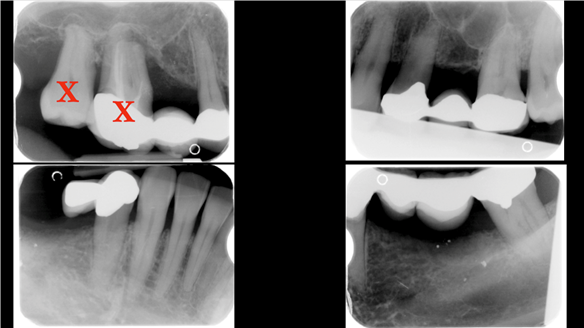

- Generalised Periodontitis; Stage 4, Grade C, Currently Unstable. Risk Factors: Type 1 diabetes. 16, 17 - hopeless prognosis. 14, 24, 26, 27, 34, 37, 44 - guarded prognosis